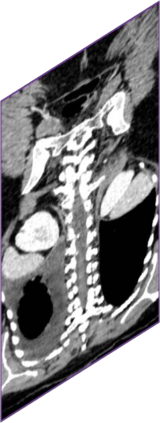

Due to the constraints of the imaging device and high cost in operation time, computer tomography (CT) scans are usually acquired with low intra-slice resolution. Improving the intra-slice resolution is beneficial to the disease diagnosis for both human experts and computer-aided systems. To this end, this paper builds a novel medical slice synthesis to increase the between-slice resolution. Considering that the ground-truth intermediate medical slices are always absent in clinical practice, we introduce the incremental cross-view mutual distillation strategy to accomplish this task in the self-supervised learning manner. Specifically, we model this problem from three different views: slice-wise interpolation from axial view and pixel-wise interpolation from coronal and sagittal views. Under this circumstance, the models learned from different views can distill valuable knowledge to guide the learning processes of each other. We can repeat this process to make the models synthesize intermediate slice data with increasing inter-slice resolution. To demonstrate the effectiveness of the proposed approach, we conduct comprehensive experiments on a large-scale CT dataset. Quantitative and qualitative comparison results show that our method outperforms state-of-the-art algorithms by clear margins.